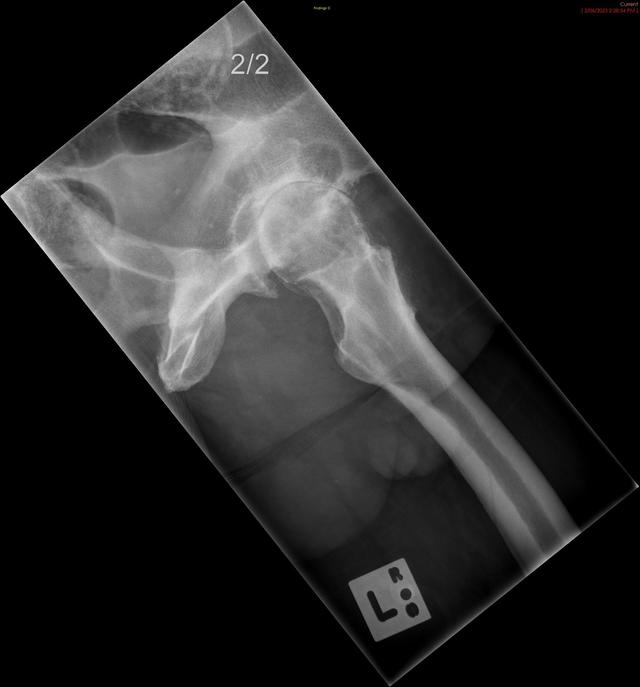

• Rex' Latest Xray

Main image

Attached is the digital image result of of Rex' Xray. The orthopedic surgeon immediately identified that he needed a total hip replacement. A cyst on his left hip was also visible in the Xray, which really causes him more pain and discomfort.